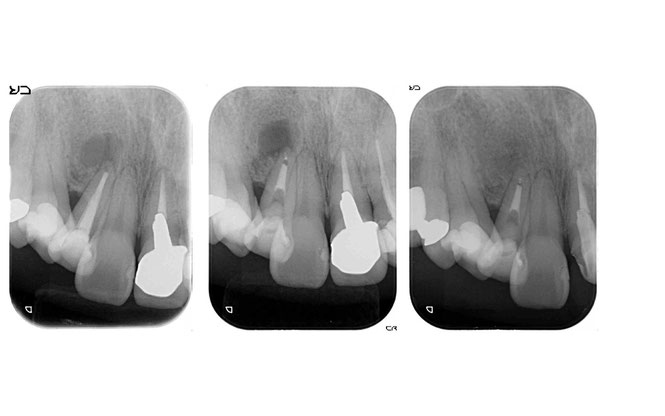

歯の根っこの先に炎症があるため歯を抜くと言われた方の根っこの再治療例です.左側が最初の状態です.根っこの先に骨が吸収して黒い丸い像が見えますが,根っこの中を消毒する事で根っこの先の黒い丸が右側の写真では無くなっています.炎症が無くなっていますので歯を抜かずにそのまま残す事ができました.